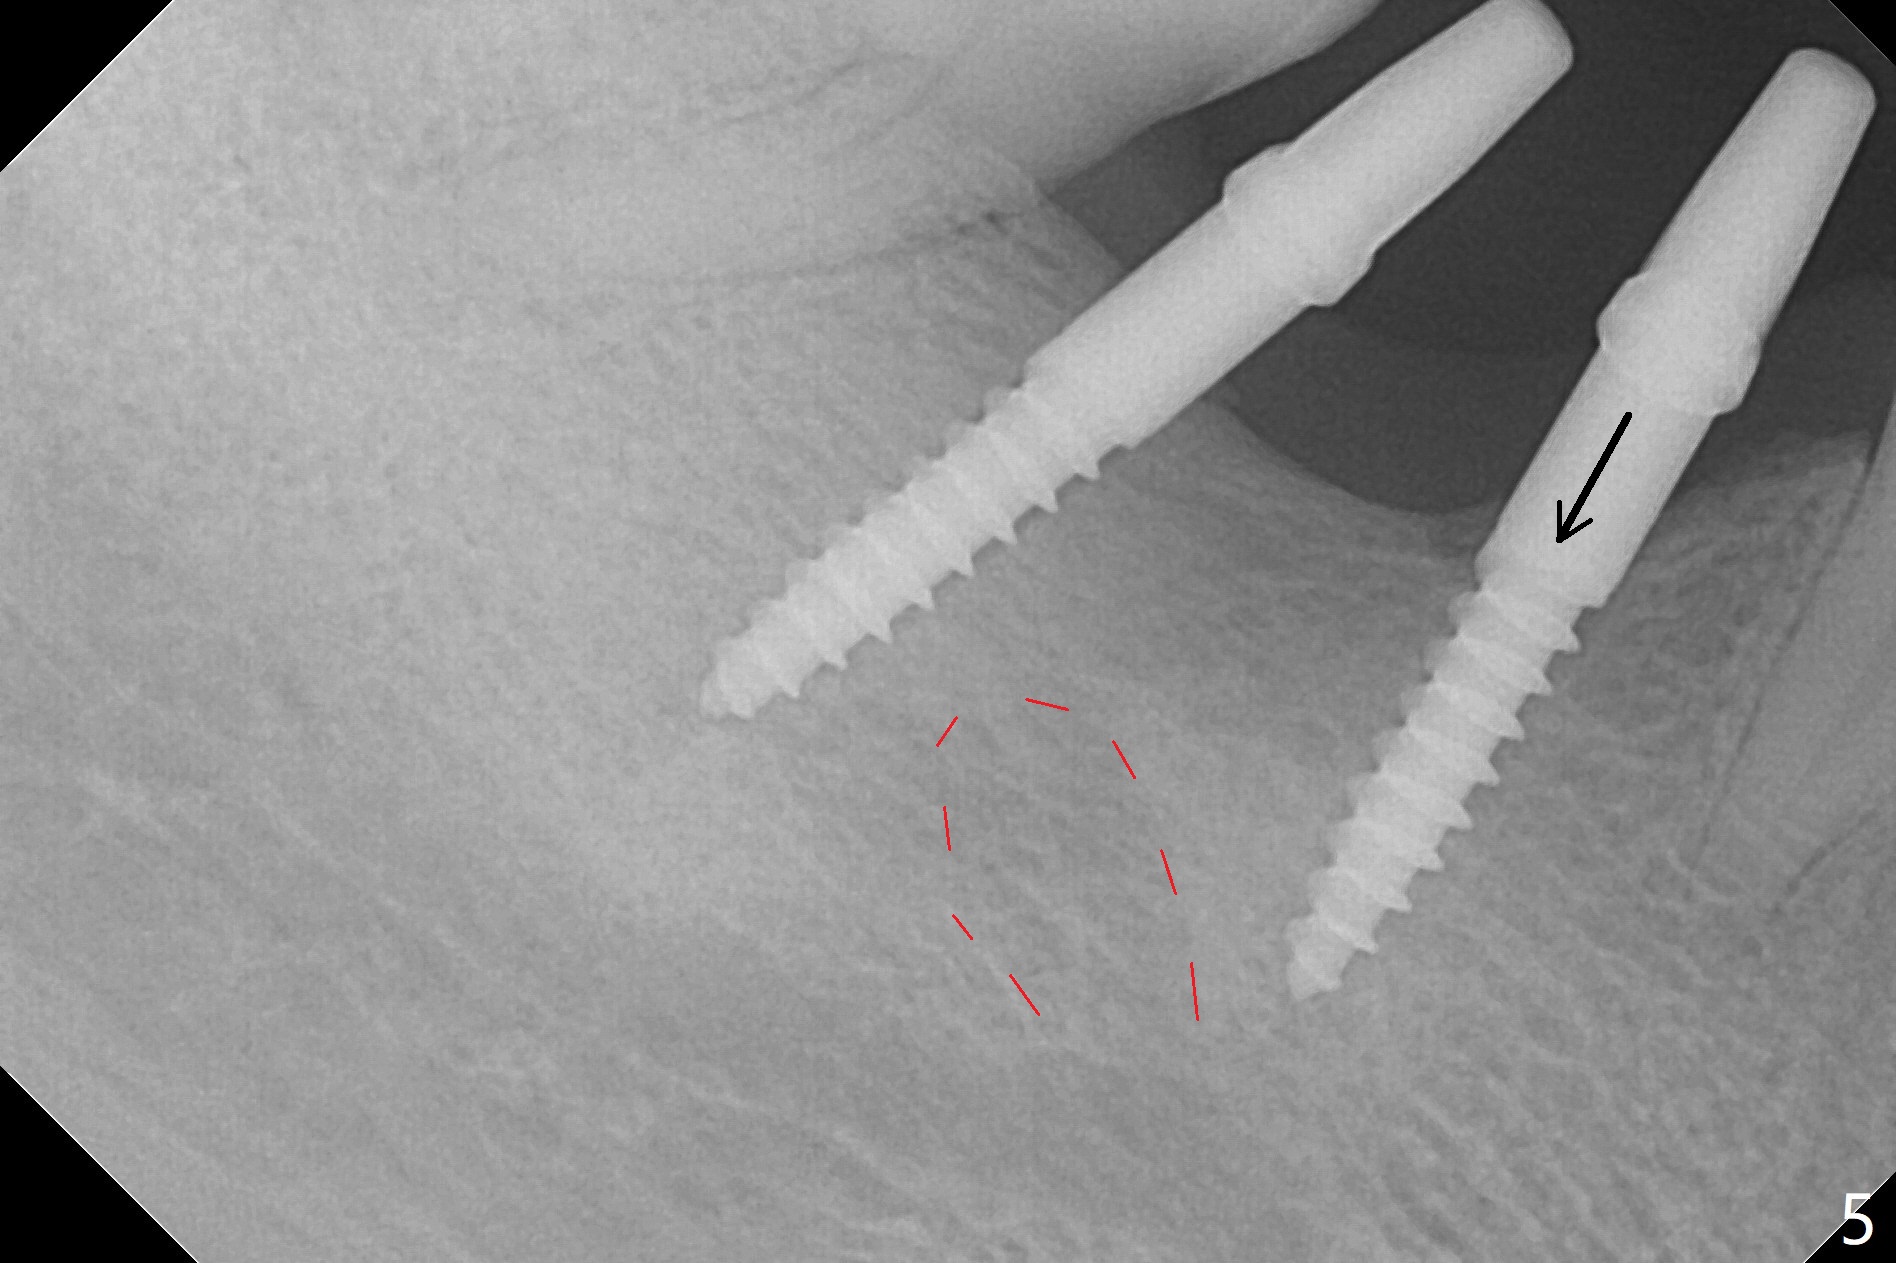

After initial osteotomy using 2.2 mm drill for 10 and 11.5 mm at #29 and 30, respectively, the guide is removed for re-insertion of drills and PA (Fig.1). The osteotomy at #29 is found lingually and in the nonkeratinized gingiva with mild laceration (wish incision to be made before osteotomy); the osteotomy is established a little lingual at #29 (Fig.2) and more or less in the middle of the narrow ridge and #30 (Fig.3). Lindamann bur is used to move #29 osteotomy buccally. A 1.5 mm drill is used to increase the depth free hand before placement of 2.5x10(4) mm 1-piece implants (Fig.4). After adjustment of the implant depth (Fig.5), CT is retaken, which shows proper implant placement (Fig.6,7). Probably due to good oral hygiene, the gingiva around the implants appears to be keratinized 4 months postop (Fig.8). After abutment preparation for margin and parallelism, impression is taken (Fig.9). When the permanent crowns are temporarily cemented, the large gingival embrasure is noted (Fig.10,11). The latter could be reduced by modifying the provisional in the healing stage. In fact the crown at #29 dislodges 2 days post cementation because lingual (Fig.12) and distal (Fig.13) placement. A surgical stent should have been fabricated from RPD for free hand placement!